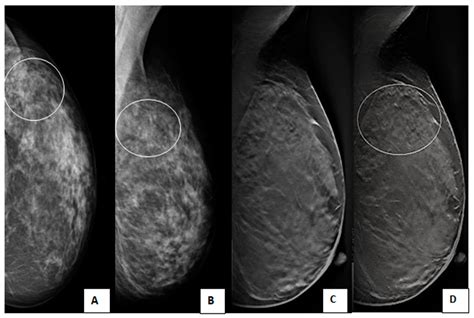

Understanding a BI-RADS 4 assessment can be stressful. Learn what this breast imaging category means, the likelihood of malignancy, and why follow-up diagnostic procedures like biopsies are often recommended. Our expert guide clarifies these medical findings, helping you navigate your breast health journey and the next steps for a definitive diagnosis with confidence and clarity.

TitleThe Impact of Adding Digital Breast Tomosynthesis to BI-RADS Categorization of Mammographically ...